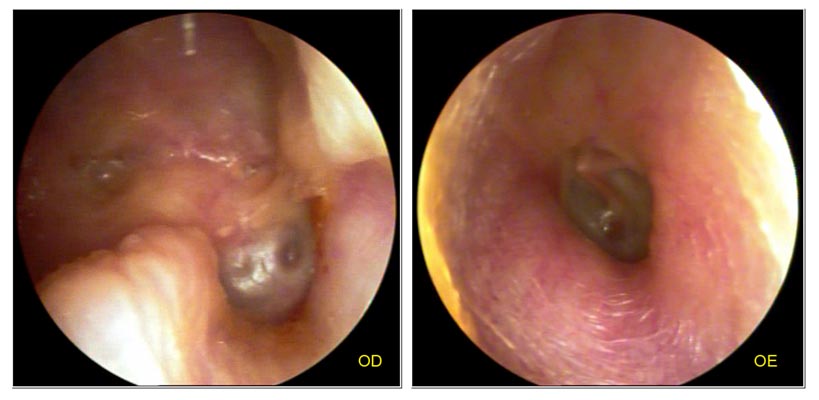

JFC otopatía supurativa crónica inactiva (der) y con colesteatoma atical (izq)

JFC Otopatía crónica bilateral con dismorfia total.

JFC Timpanoplastia radical derecha.